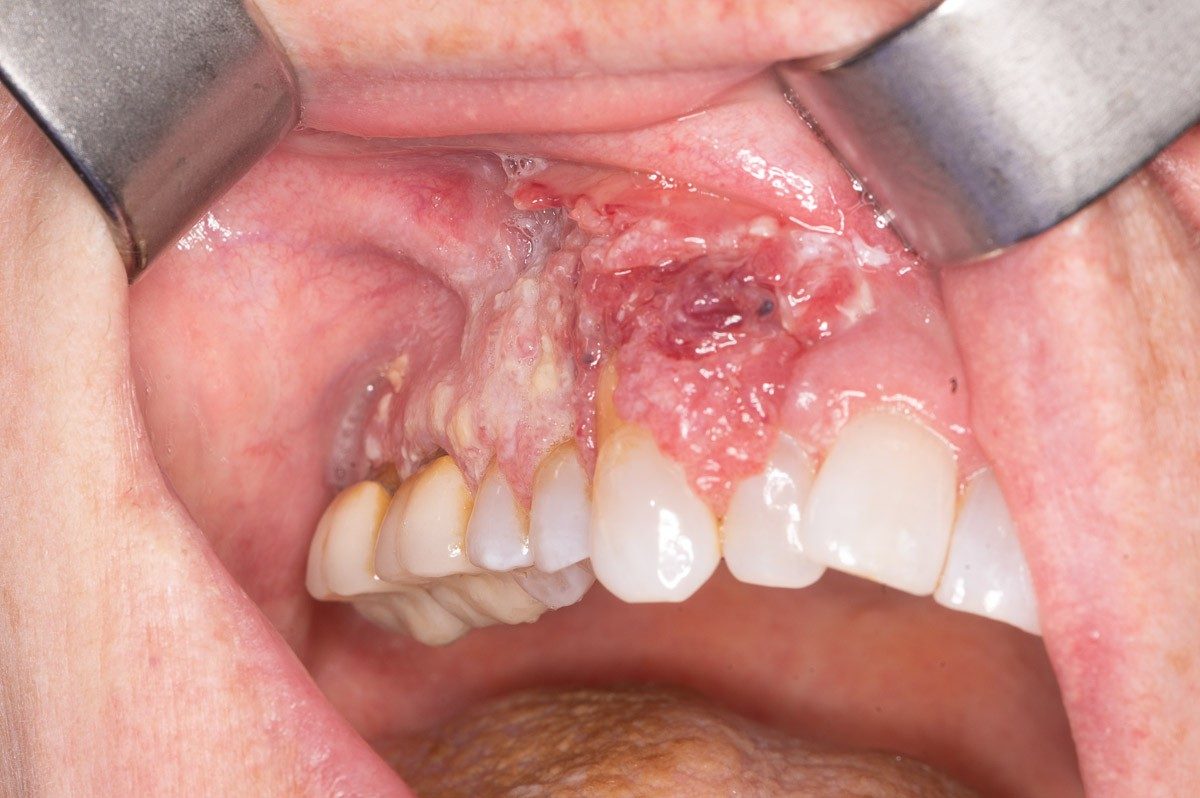

A cancer of the upper gingiva, or gum.

Cancer of the lower gums, behind the front teeth.